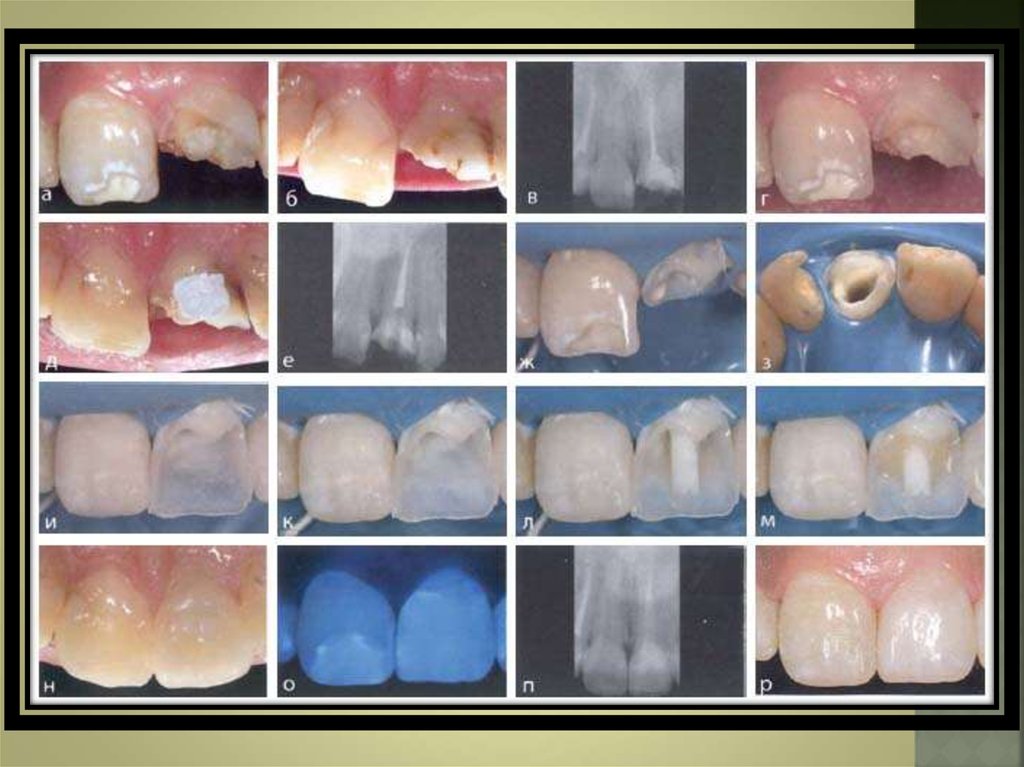

14. Шыныталшықты штифтті орнатудың клиникалық кезеңдері:

Эндодонтиялық емді аяқтаған соң барлық

кариозды тіндерді алу керек.

Gates-Glidden бұрғысы көмегімен штифтке орын

дайындайды.

Түбір өзегінің дентинін 2 минут көлемінде 37%

ортофосфорлы қышқылмен уландырады. Сосын түбір

өзегін эндодонтиялық ине көмегімен сумен шаяды.

Бұл кезеңде талшықты штифтті түбірге өлшеп көреді,

егер қысқарту керек болса алмазды диск көмегімен

қысқартылады. Кейіннен түбір өзегінің дентинін

кептіріп, шамалы мөлшерде ылғалдандырады және

катализаторы бар эмаль-дентинді адгезив жағылады.

Фиксациялайтын цемент есебінде ине арқылы

енгізілетін екі реттік қатаятын композитті

қолданған дұрыс.

Шыныталшықты штифт орнатылады.

Композиттің полимеризациясын жүргізеді.

17. Микрогибридті композит көмегімен тұқылды құруға кіріседі. Егер тіс кейіннен жасанды сауытпен жабылатын болса тіс анатомиясына